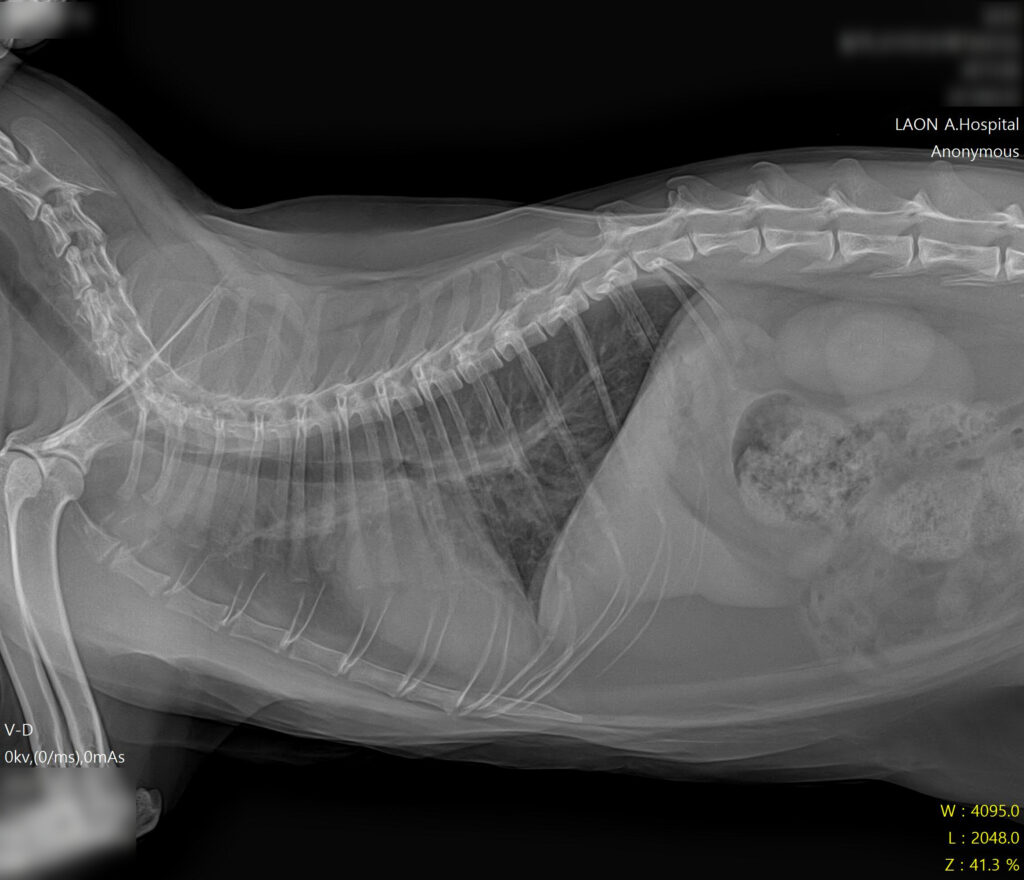

* 폐수종 개선 및 깨끗해진 폐야 확인

보호자님께는 HCM이 완치가 아닌 평생 관리가 필요한 질환임을 설명드렸습니다. 매일 정해진 시간에 약을 복용하는 것이 가장 중요하며 흥분이나 스트레스를 피하고 정기적인 검진(초음파, X-ray)을 통해 심장 상태를 추적하기로 했습니다.